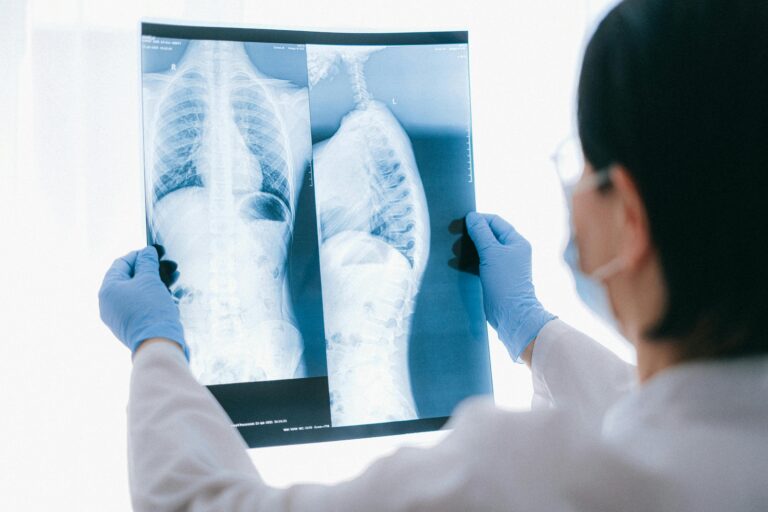

Cervical Disc Conditions

Cervical disc problems may develop from aging, injury, or repetitive strain. Symptoms can include stiffness, radiating arm pain, numbness, or reduced range of motion.

Nerve-Related Neck Conditions

Nerve compression in the cervical spine can cause radiating pain, numbness, or weakness extending into the shoulders and arms.